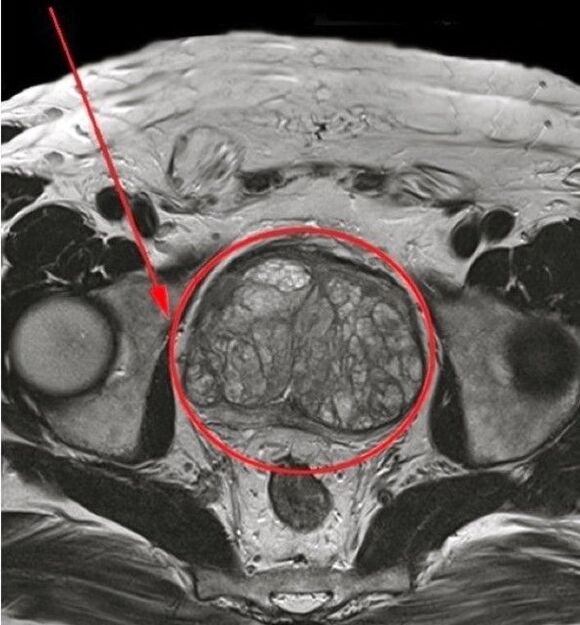

Okrenuo sam se liječniku, razumijevajući važnost pravovremenog liječenja. Na temelju rezultata ispitivanja, dijagnosticiran mi je kronični prostatitis. Specijalist mi je preporučio da prođem tijek liječenja prirodnim lijekom Predstonorm U kapsulama.